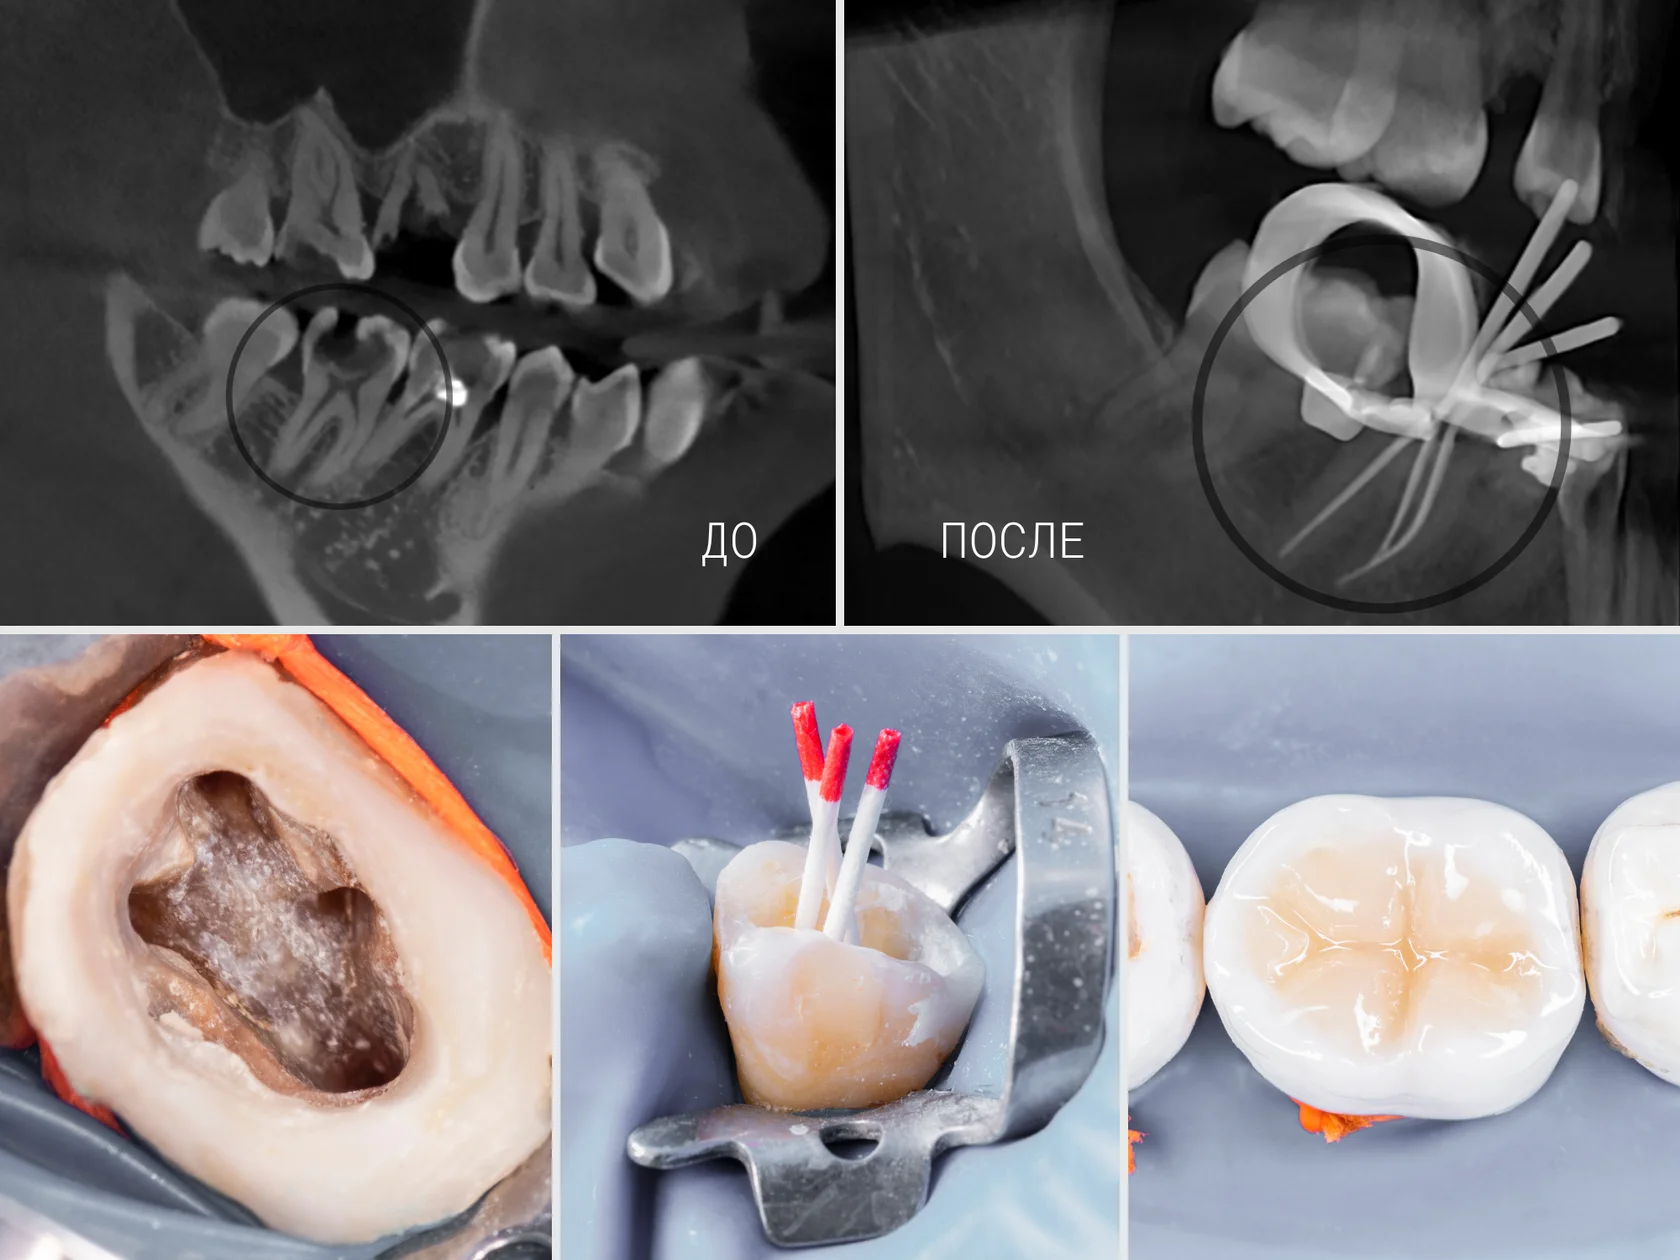

Пациент пришел с острой пульсирующей болью. Диагностика выявила глубокий кариес с воспалением нерва. Для точного планирования лечения потребовалась КЛКТ.

1. КЛКТ-диагностика — трёхмерное сканирование выявляет анатомию всех каналов

2. Установка кофердама — абсолютная изоляция создаёт стерильное поле

3. Удаление воспалённой пульпы — извлечение нерва и промывание антисептиками

4. Прохождение каналов под контролем КЛКТ — используя данные томографии, врач проходит каждый канал, не пропуская скрытые

5. Многократная промывка и высушивание — дезинфекция и идеальное высушивание благодаря кофердаму

6. Герметичное пломбирование гуттаперчей — каналы заполняются до верхушки корня без пустот

7. Восстановление коронки фотокомпозитом — анатомия зуба полностью восстанавливается

8. Контрольная КЛКТ — подтверждает идеальное заполнение всех каналов

- Зуб спасён — своевременное лечение предотвратило удаление

- Все каналы найдены — КЛКТ исключила пропущенные каналы

- Абсолютная стерильность — кофердам предотвратил инфицирование

- Идеальное заполнение — каналы герметично запломбированы

- Вероятность успеха 95%+ — на 10-15 лет

- Нет боли — стерильность исключает воспаление